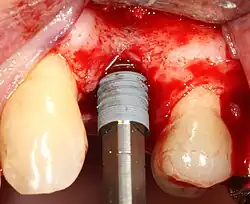

A series of slow-speed drills create and gradually enlarge a site in the jaw for the implant to be placed. The hole is called an osteotomy.

Once the bone is exposed, a series of drills create and gradually enlarge a site (called an osteotomy) for the implant to be placed.

The implant fixture is turned into the osteotomy. Ideally, it is completely covered by bone and has no movement within the bone.

2. Drilling at high speed: After reflecting the soft tissue, and using a surgical guide or stent as necessary, pilot holes are placed with precision drills at highly regulated speed to prevent burning or pressure necrosis of the bone.

3. Drilling at low speed: The pilot hole is expanded by using progressively wider drills (typically between three and seven successive drilling steps, depending on implant width and length). Care is taken not to damage the osteoblast or bone cells by overheating. A cooling saline or water spray keeps the temperature low.

4. Placement of the implant: The implant screw is placed and can be self-tapping;[50]:100–102 otherwise, the prepared site is tapped with an implant analog. It is then screwed into place with a torque controlled wrench[54] at a precise torque so as not to overload the surrounding bone (overloaded bone can die, a condition called osteonecrosis, which may lead to failure of the implant to fully integrate or bond with the jawbone).